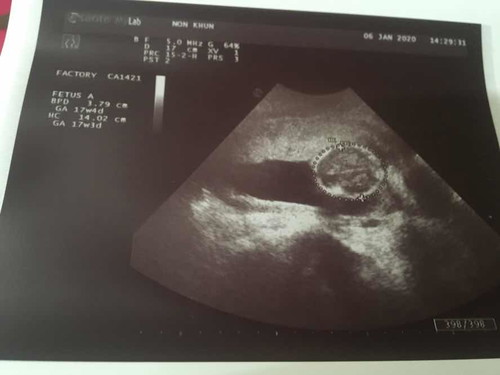

ท้องได้ 19 w5dเเล้วค่ะ พึ่งได้ซาวครั้งเเรก หมอไม่ได้พูดอะไรเลยนอกจากว่ายังไม่ทราบเพศนะคะ อยากรู้คะว่าน้องอยู่ตรงไหน มองไม่ออกเลยค่ะ

ภาพหมอวัดกระโหลกศรีษะค่ะ ไม่เห็นตัวน้อง